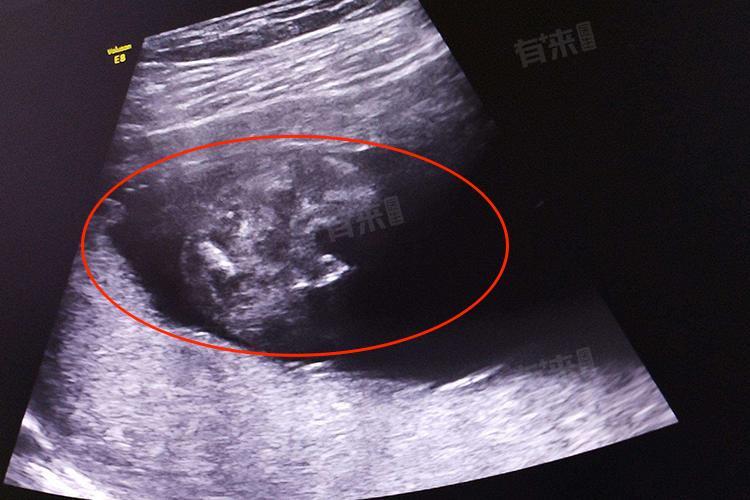

3、借助医疗设备:超声检查是孕期常用的检查手段,孕15周时通过超声可清晰看到胎儿的形态、结构及活动情况,能直观确认胎儿的存在与发育状况。此外,使用多普勒胎心仪可在孕妇腹部特定位置听到胎儿心跳声,正常胎心率为110-160次/分钟。超声和胎心仪检查不仅能让孕妇从科学角度感受胎儿存在,还可早期发现胎儿发育异常,为孕期保健提供重要依据。